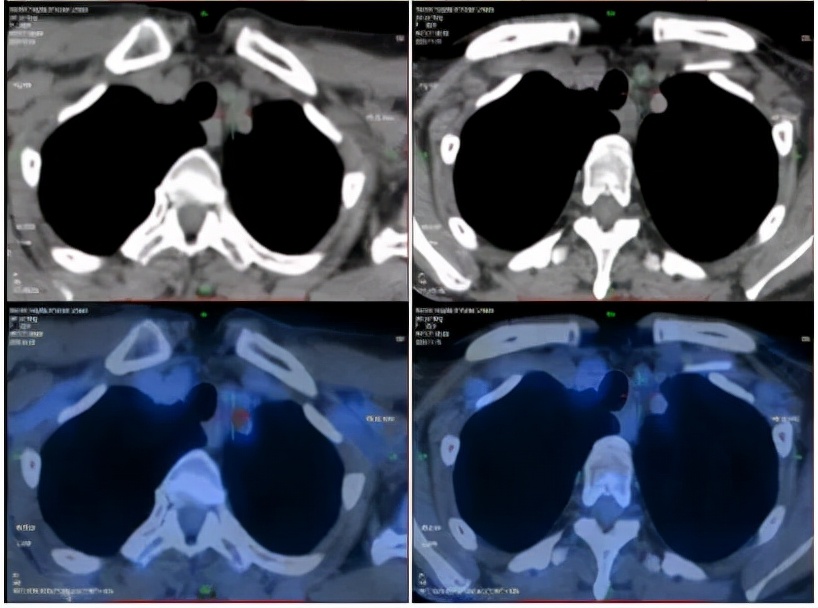

2020-4-22PET-CT提示:1. 胰腺体尾部稍低密度团块;肝内见多发团块、结节灶;肝门区、胰腺周围、腹膜后区多发肿大淋巴结;全身多发骨质密度不均;上述病灶代谢增高,考虑恶性病变,胰腺癌伴全身多发转移;2. 左锁骨上区及胸廓入口处淋巴结,代谢稍增高;不除外转移可能。

PET-CT(2020-04-22)

2020-11-18PET-CT提示:1.胰腺体部结节,代谢增高;肝实质多发稍低密度团块、结节灶,代谢增高;全身多发骨质密度不均,代谢稍增高;上述考虑胰腺癌伴多发转移灶治疗后改变,少许活性尚存。2.左锁骨上区及胸廊入口处淋巴结,较前缩小,代谢减低;肝门区、胰腺周围及腹膜后区高代谢淋巴结未见明显显示;上述考虑转移灶经治疗后改变,活性受抑

2020-4-22 2020-11-18